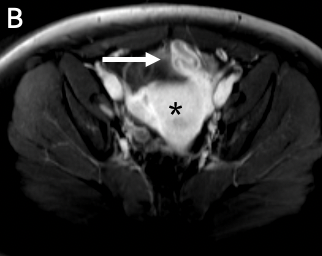

Approximately 1 month later, the patient followed up for a repeat pelvic ultrasonography scan, which showed a reaccumulation of pelvic fluid in the area of the previous left tubo-ovarian abscess (Figure 3). Repeat laboratory studies showed a persistent elevation in C-reactive protein level of 9.38 mg/dL. She was readmitted to the hospital and underwent drainage of pelvic fluid by an interventional radiologist, which revealed a left-sided tubo-ovarian abscess. Results of a fluoroscopy raised concern for a noncommunicating left uterine horn. However, a repeat pelvic MRI did not show evidence of a noncommunicating left uterine horn. A repeat peritoneal fluid culture grew Bacteroides thetaiotaomicron. This time, the patient received ampicillin/sulbactam, 2000 mg, every 6 hours and was discharged with amoxicillin, 875 mg, and clavulanic acid, 12 mg, every 12 hours to complete another 14-day course. She was also placed on an oral contraceptive.

Figure 3. Transverse (A) and sagittal (B) ultrasonography scans of the pelvis demonstrated a thick-walled hypoechoic structure containing internal debris in the left lower quadrant, consistent with pyosalpinx related to recurrent tubo-ovarian abscess (arrows).